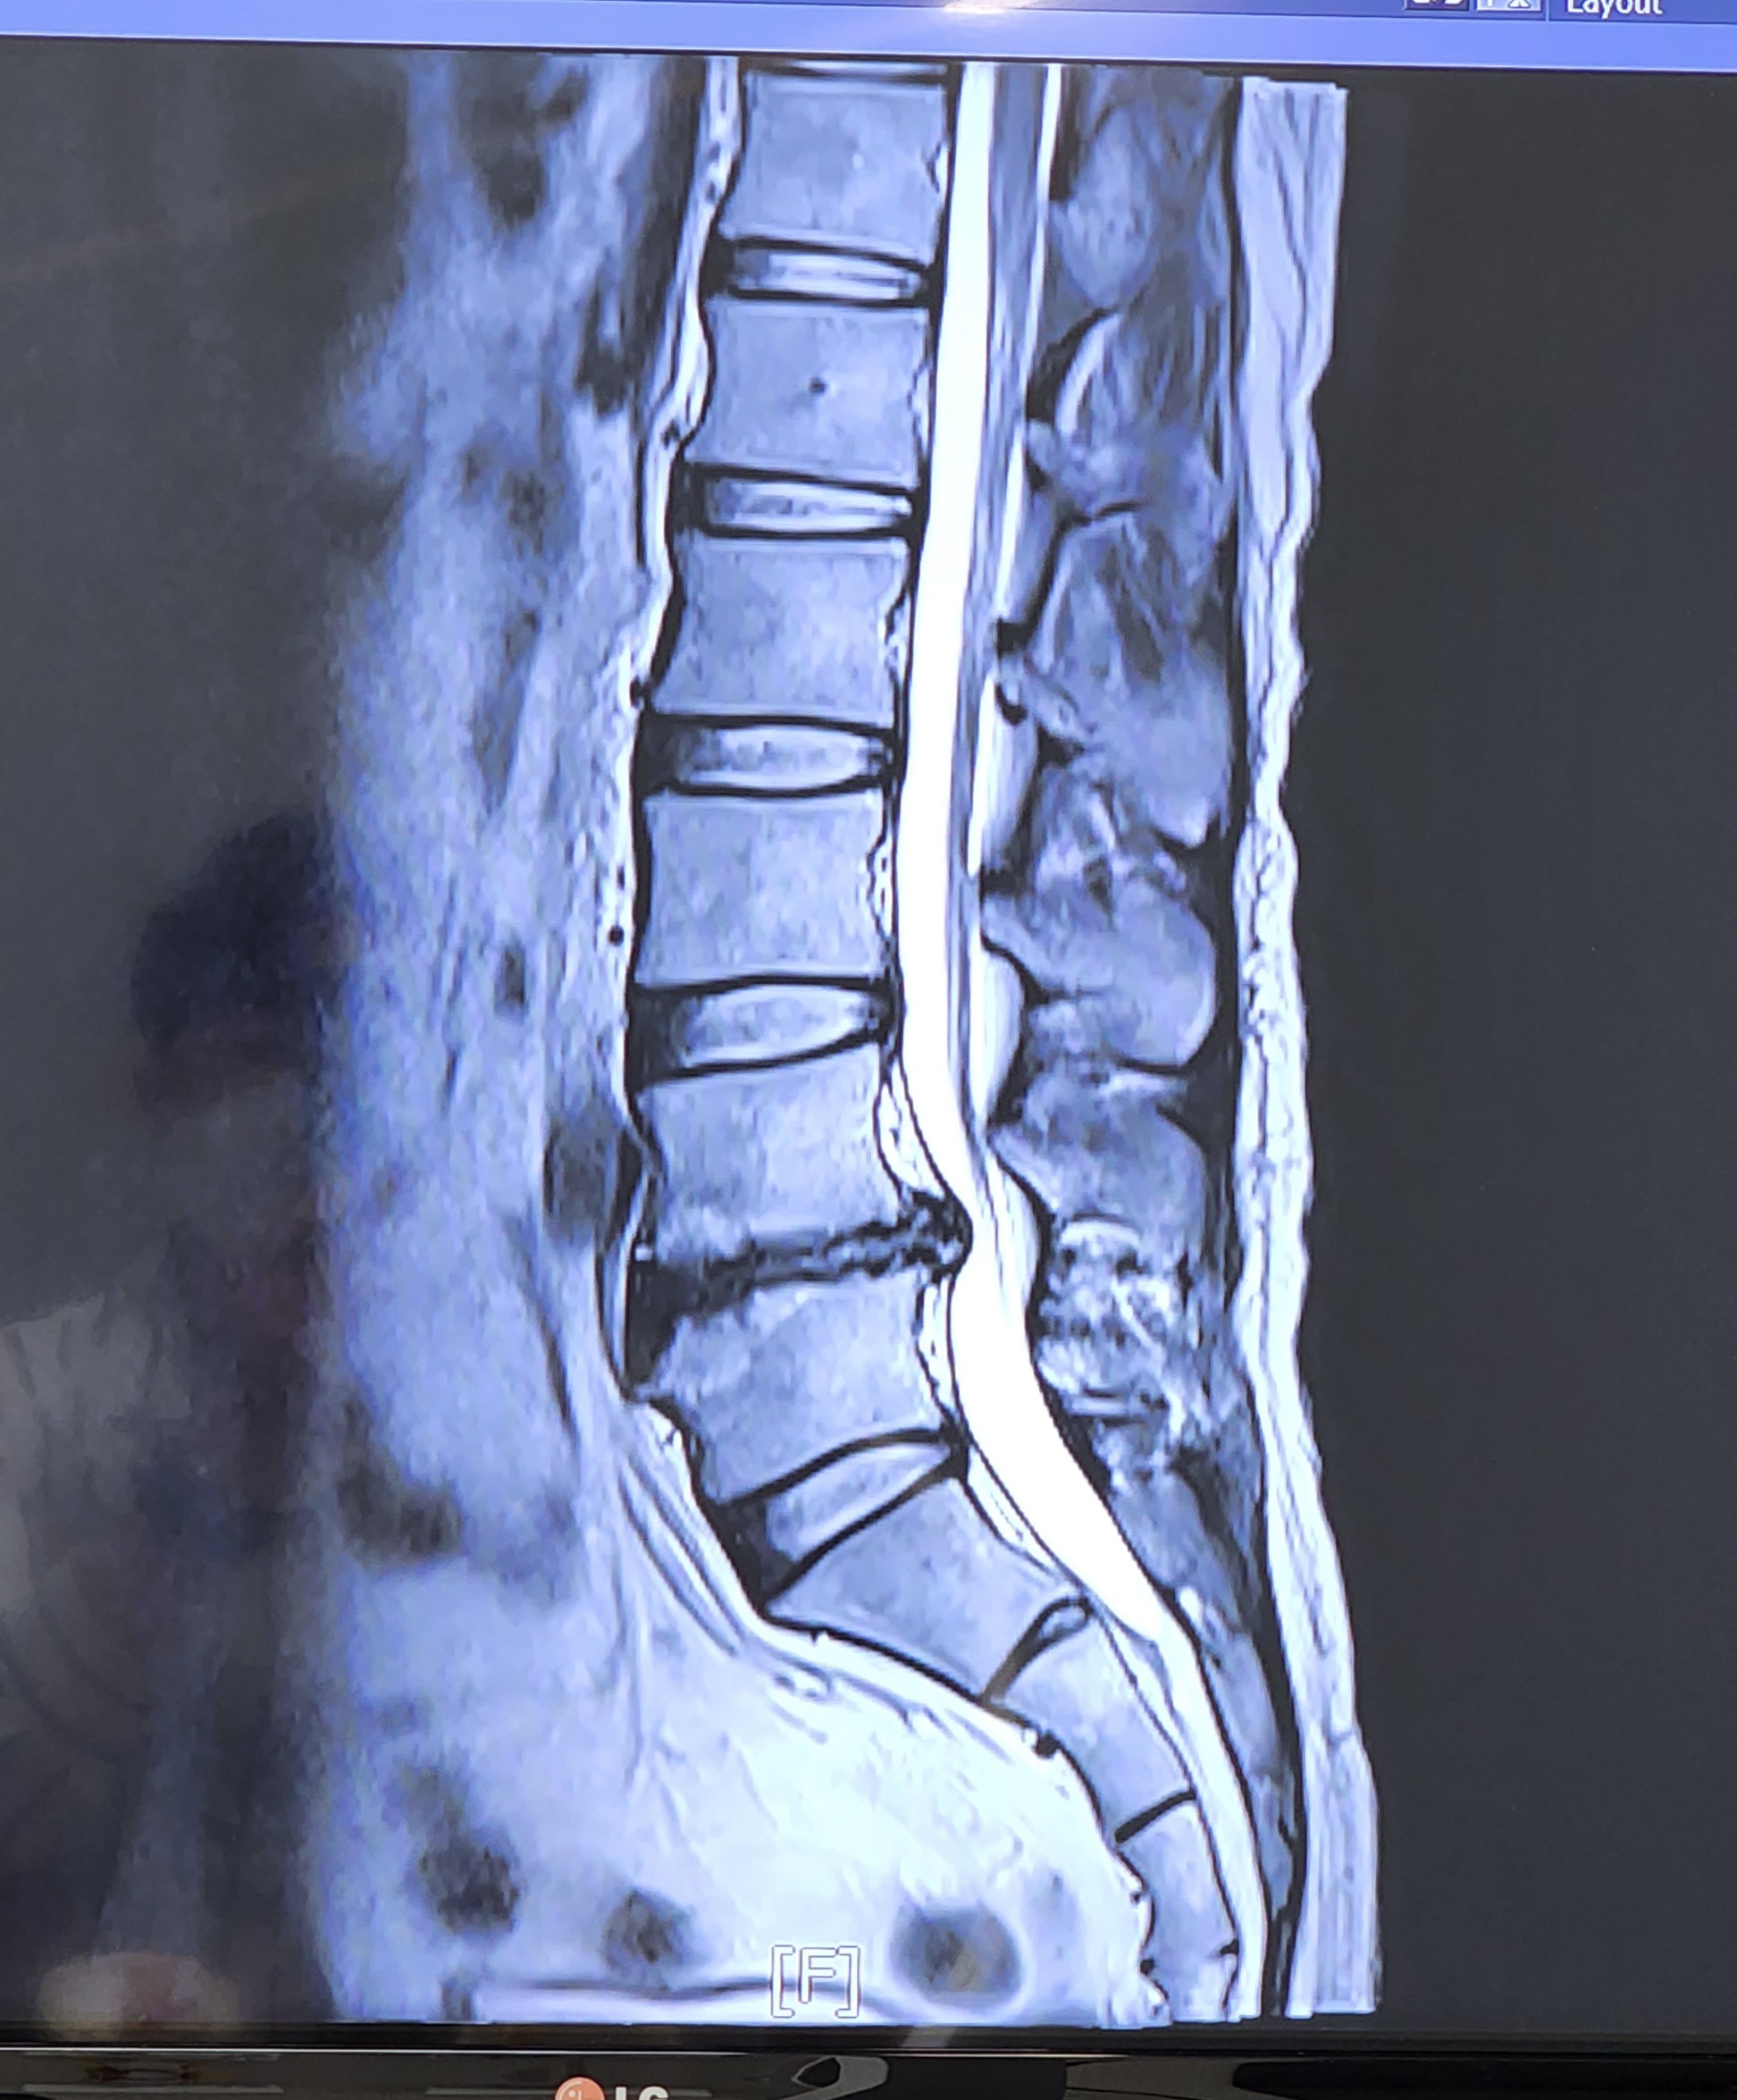

³ªµµ µð½ºÅ© ȯÀڷνá Á¶±×¸¸ÇÑ Á¶¾ð ÇѸ¶µð ÇÒ²² ¿ì¼± »çÁø°ú °°ÀÌ ³ªµµ ¾öû ¾ÆÇÁ°í ¾ÆÄ§¿¡ ÀϾ¸é Ç㸮¾ÆÆÛ¼ ¸öÀ» °¡´©Áú ¸øÇؼ ÀÛÀº º´¿øºÎÅÍ Àü¹®º´¿ø Áö±ÝÀº ¼¿ï¾Æ»êº´¿ø ´Ù´Ï°í ÀÖ¾î ½Ã¼ú ¸¹ÀÌ ÇØº¸°í ¼ö¼ú±îÁö »ý°¢Çߴµ¥ º´¿ø¿¡¼´Â ¿îµ¿À¸·Î ±Øº¹Ç϶ó´Â°Å¾ß ¾ÆÆÛÁװڴµ¥ ¹«½¼ ±Øº¹ÀÌ µÇ³Ä ¶ó°í »ý°¢ÇÏ¸é¼ ¸¶¾àÁøÅëÁ¦ ¸ÔÀ¸¸é¼ Á¶±Ý¾¿ ÅëÁõÀÌ ¾ø¾îÁö´õ¶ó°í (µð½ºÅ©´Â 70%±îÁö ÀÚ°¡È¸º¹µÊ ÀÎü½Åºñ) ±×·¡¼ º´¿ø¿¡¼ ¾Ë·ÁÁØ ¿îµ¿ ²ÙÁØÈ÷ Çß¾î ±×·¨´õ´Ï È®½ÇÈ÷ ÁÁ¾ÆÁ³°í Áö±ÝÀº ¸¶¾àÁøÅëÁ¦ °ÅÀÇ ¾È¸Ô¾îµµ µÉÁ¤µµ±îÁö ¿ÔÁö¸¸ º´¿ø¿¡¼´Â ¾È¸ÔÀ»Á¤µµ·Î ´õ ¿îµ¿Ç϶ó°í ÇÏÁö¸¸ ÀÏÇϰí¿À¸é ÇǰïÇØ¼ À߸øÇÏ´ÂÁß ¤Ì¤Ì